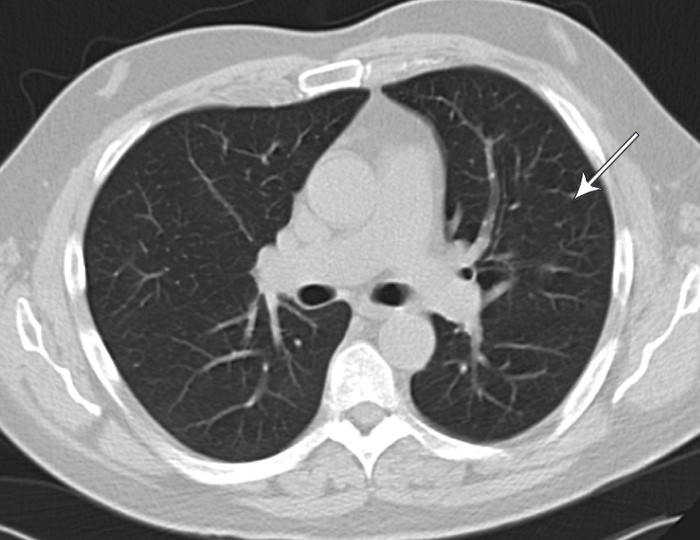

Nye episoder med global hodepine av pressende karakter, CRP-stigning og sensoriske symptomer i høyre kroppshalvdel samt epileptiske anfall i de kommende tre ukene førte til to reinnleggelser med nye antibiotikakurer og oppstart av antiepileptisk medikasjon. Gjentatte cerebrospinalvæskeanalyser viste uendrede funn, infeksiøst agens i cerebrospinalvæsken eller andre kroppsvæsker kunne ikke påvises. MR-kontroll viste økende venstresidig kortikalt hjerneødem. Med tanke på mulig epi- eller subduralt empyem ble det utført eksplorativ kraniotomi med meningeal biopsi. Makroskopisk fant man normalfarget, men hard og tykk dura samt leddblødende subduralt granulasjonsvev. Histologi viste fortykket dura med fibrose og uspesifikt inflammatorisk infiltrat (fig 2). Mikrobiologiske undersøkelser var normale. I et tverrfaglig møte der infeksjonsmedisiner, nevrolog, øre-nese-hals-lege, øyelege, revmatolog, nevrokirurg, nevroradiolog og nevropatolog deltok, ble det konkludert med at pasientens symptomer mest sannsynlig var betinget i intrakranial hypertrofisk pakymeningitt.